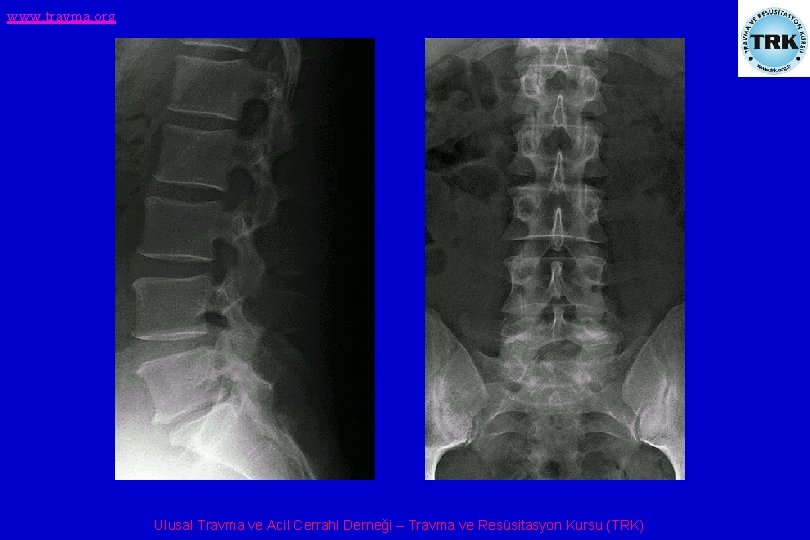

www. travma. org Direkt grafi • • • Torakal ve/veya lomber yaralanmada Pediküllerin iki yanlı simetrisi Omurlarası disk mesafesinin yüksekliği Spinoz çıkıntılarının orta hatta olup olmadığı Omurların konturları Omurga düzlemi Ulusal Travma ve Acil Cerrahi Derneği – Travma ve Resüsitasyon Kursu (TRK)

www. travma. org Omurga yaralanmaları • T 11 -L 1 kırıkları: Mekanizma çoğu kez ani hiperfleksiyon ve rotasyon kombinasyonu şeklindedir. Çoğu kez anstabildir. • Lomber kırıklar: Çoğu kez ani hiperfleksiyon sonucu oluşurlar. Ulusal Travma ve Acil Cerrahi Derneği – Travma ve Resüsitasyon Kursu (TRK)